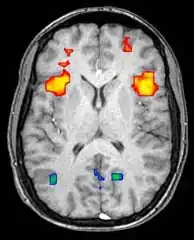

Axial MRI slice at the level of the basal ganglia, showing fMRI BOLD signal changes overlaid in red (increase) and blue (decrease) tones

Functional magnetic resonance imaging (fMRI) and arterial spin labeling (ASL) relies on the paramagnetic properties of oxygenated and deoxygenated hemoglobin to see images of changing blood flow in the brain associated with neural activity. This allows images to be generated that reflect which brain structures are activated (and how) during the performance of different tasks or at resting state. According to the oxygenation hypothesis, changes in oxygen usage in regional cerebral blood flow during cognitive or behavioral activity can be associated with the regional neurons as being directly related to the cognitive or behavioral tasks being attended.